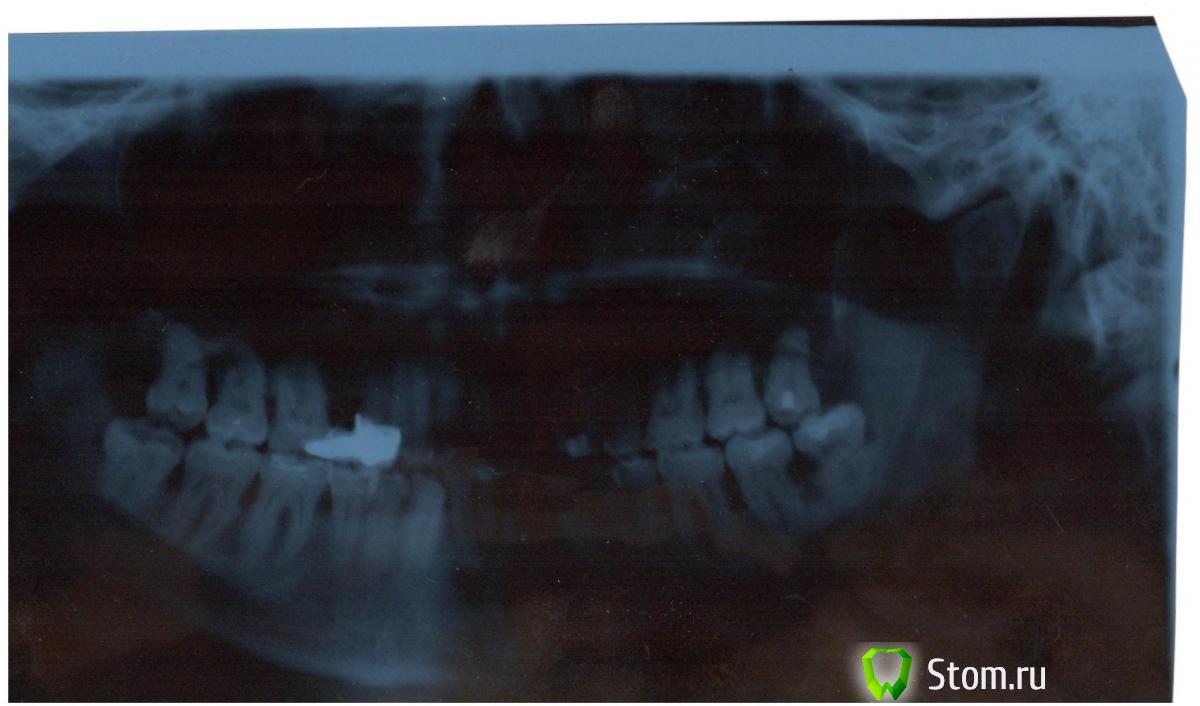

IgorM Опубликовано 18 января, 2012 Поделиться Опубликовано 18 января, 2012 Добрый день . Подскажите пожалуйста какие есть технологии лечения кариеса корней зубов ? В нескольких клиниках в г Новосибирск, мне сказали что в моем случае (см. снимок - 8(последний) и 7 зубы справа снизу) необходимо удаление двух этих зубов , а возможности поставить имплантант - нет.. Если кто-то специализируется на данной проблеме - подскажите пожалуйста что можно сделать в моем случае.. Заранее благодарен. мой e-mail: realflex@inbox.ru Ссылка на комментарий

Ayrat_zub Опубликовано 2 февраля, 2012 Поделиться Опубликовано 2 февраля, 2012 (изменено) А если, попробовать сначала удалить семерку .. ведь наверное больше шансов на его место поставить имплантант и более удобно - если попытаться лечить восьмой зуб.. Каково Ваше мнение ?вероятность то есть вылечить кариес, но высока вероятность получить полсле лечения "проблемы с деснами" в этом месте, которые там, судя по снимку уже есть... Изменено 2 февраля, 2012 пользователем Ayrat_zub Ссылка на комментарий

Sib-oboima Опубликовано 3 февраля, 2012 Поделиться Опубликовано 3 февраля, 2012 уважаемые коллеги, поправте меня если ошибаюсь. возможно поступить таким образом-удалить 8, а на семерке гемисекцию. и одиночную простенькую короночку Ссылка на комментарий

shishok Опубликовано 3 февраля, 2012 Поделиться Опубликовано 3 февраля, 2012 В данном случае гемисекция не выход-между шестым и седьмым тоже значительная убыль костной ткани,и семёрка более-менее устойчива из-за наличия 2х корней.Если один убрать(гемисекция),второй "полетит"следом. Ссылка на комментарий